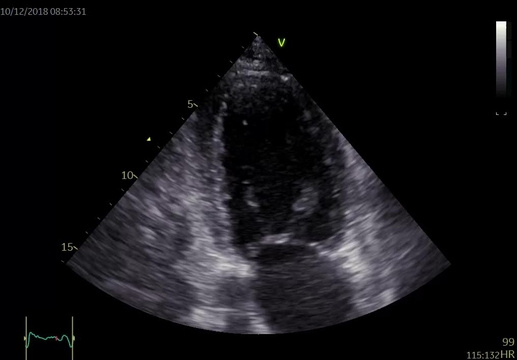

Při fyzikálním vyšetření měla nemocná TK 115/70 mm Hg, pravidelný puls 100/min, poslechově na plicích inspirační chrůpky při bázích a systolický šelest v prekordiu s maximem na hrotu, bez jasné propagace, intenzity 3/6. Dolní končetiny jsou se symetrickými perimaleolárními otoky, klidné varixy. Na EKG byla přítomna sinusová tachykardie 105/min, EKG kritéria hypertrofie levé komory s mírnými repolarizačními změnami, bez signifikantní ST denivelizace a abnormalita levé síně (obrázek 1). Echokardiografie prokázala dilataci a excentrickou hypertrofii levé komory (LVEDD 63 mm, LVMI 102 g/ m2, relativní tloušťka stěn 0,35), difúzní hypokinezi stěn výraznější v oblasti septa a těžkou systolickou dysfunkci levé komory s EF 24 %. Diastolická funkce měla charakter pseudonormalizace se zvýšenými plnicími tlaky levé komory (E/e'průměr 13). Dále byla zjištěna středně významná sekundární mitrální regurgitace 2–3+ při dilataci anulu a restrikci cípů v důsledku remodelace levé komory a sekundární trikuspidální regurgitace 2–3+ při dilataci anulu (video 1 a 2). Levá síň byla dilatována s indexovaným objemem 48 ml/m2 a zvýšena byla tenze v plicnici s odhadem PASP 49 mm Hg. Laboratorně prokázána elevace NT-proBNP 4 170 ng/l, mírná hypokalémie 3,6 mmol/l, kreatinin 112 μmol/l s mírně sníženou glomerulární filtrací 70 ml/min/1,73 m2 dle MDRD.

Video 1. Echokardiografické vyšetření, apikální čtyřdutinová projekce (1A) a dvoudutinová projekce (1B) – dilatace a významná systolická dysfunkce levé komory s EF 24 %